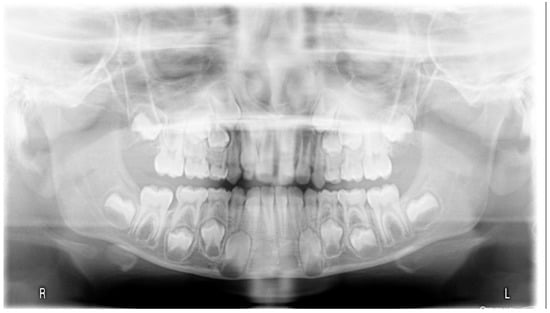

3.1. Clinical Case #1

3.2. Clinical Case #2

3.3. Clinical Case #3

3.4. Clinical Case #4